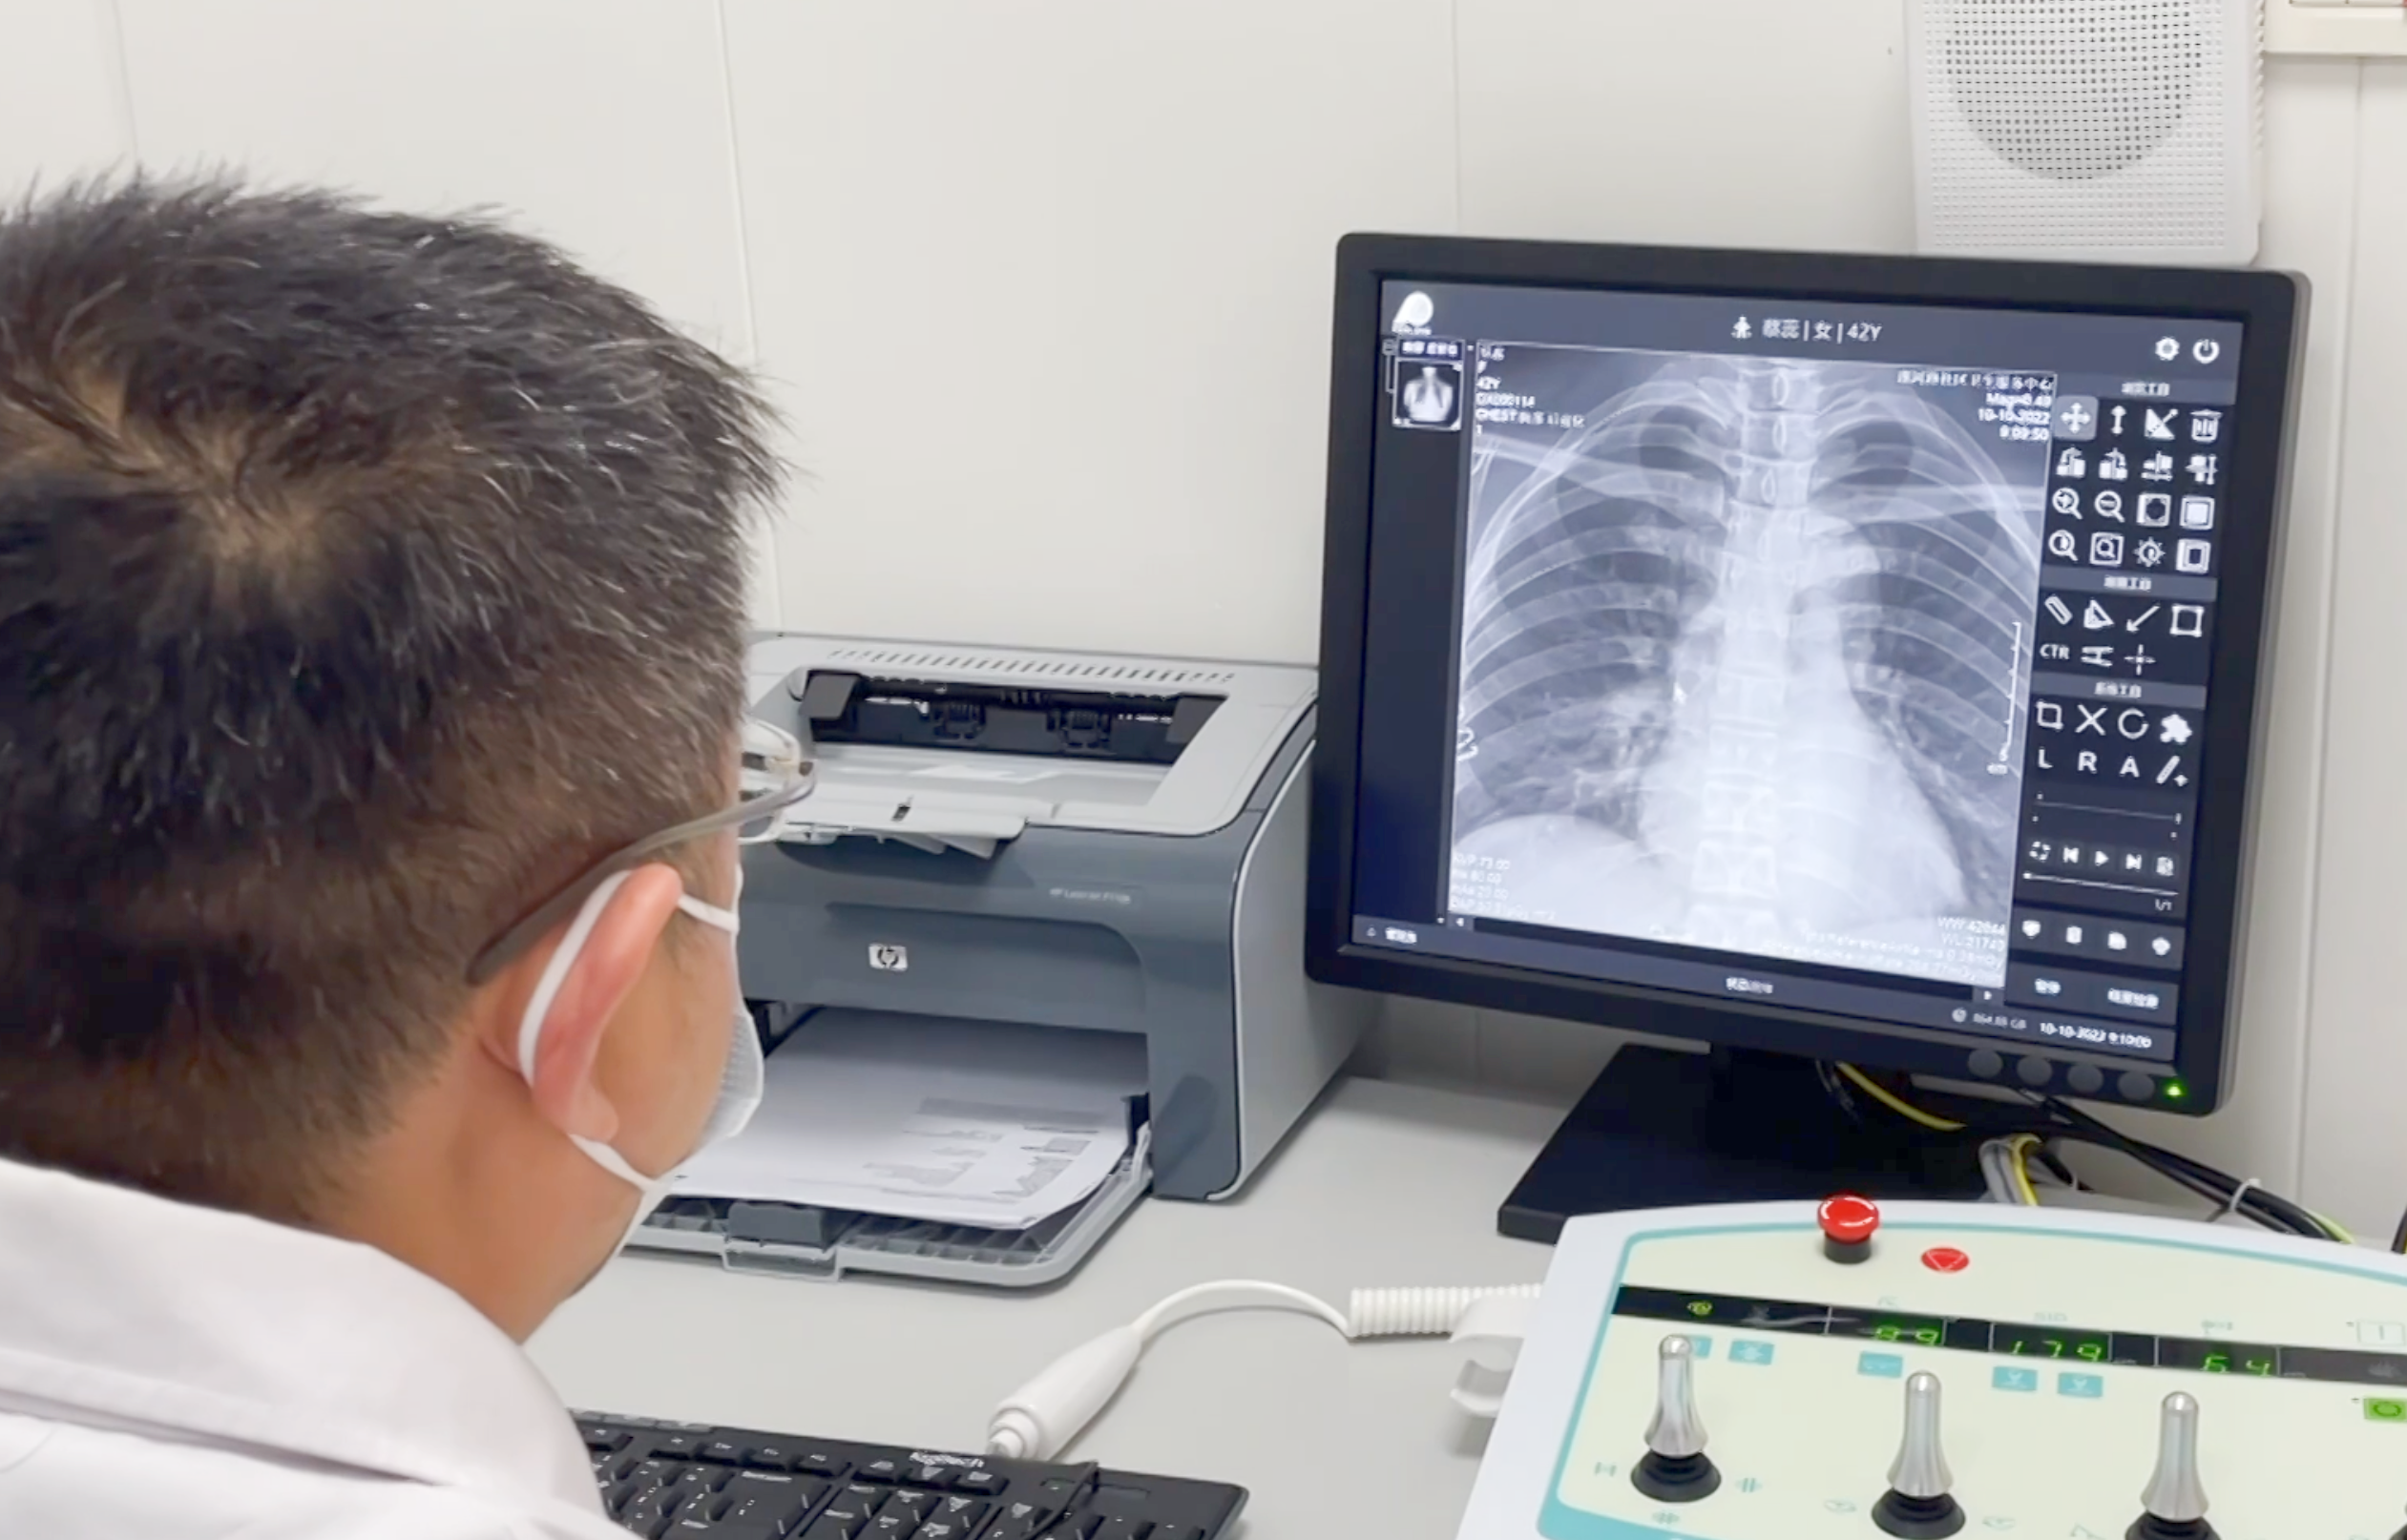

動(dòng)態(tài)DRF以革新的動(dòng)態(tài)平板探測(cè)器作為全新的數(shù)碼載體,臨床應(yīng)用廣泛,在婦幼檢查中有著重要的臨床價(jià)值。

康復(fù)是治療的延伸,老年人和肢體損傷性患者是康復(fù)醫(yī)院常見的患者類型,動(dòng)態(tài)DRF與普通X線影像相比圖像質(zhì)量分辨率高、灰階度廣、圖像信息量大,有助于提高診斷準(zhǔn)確率,為上述患者的康復(fù)之路提供基礎(chǔ)保障!